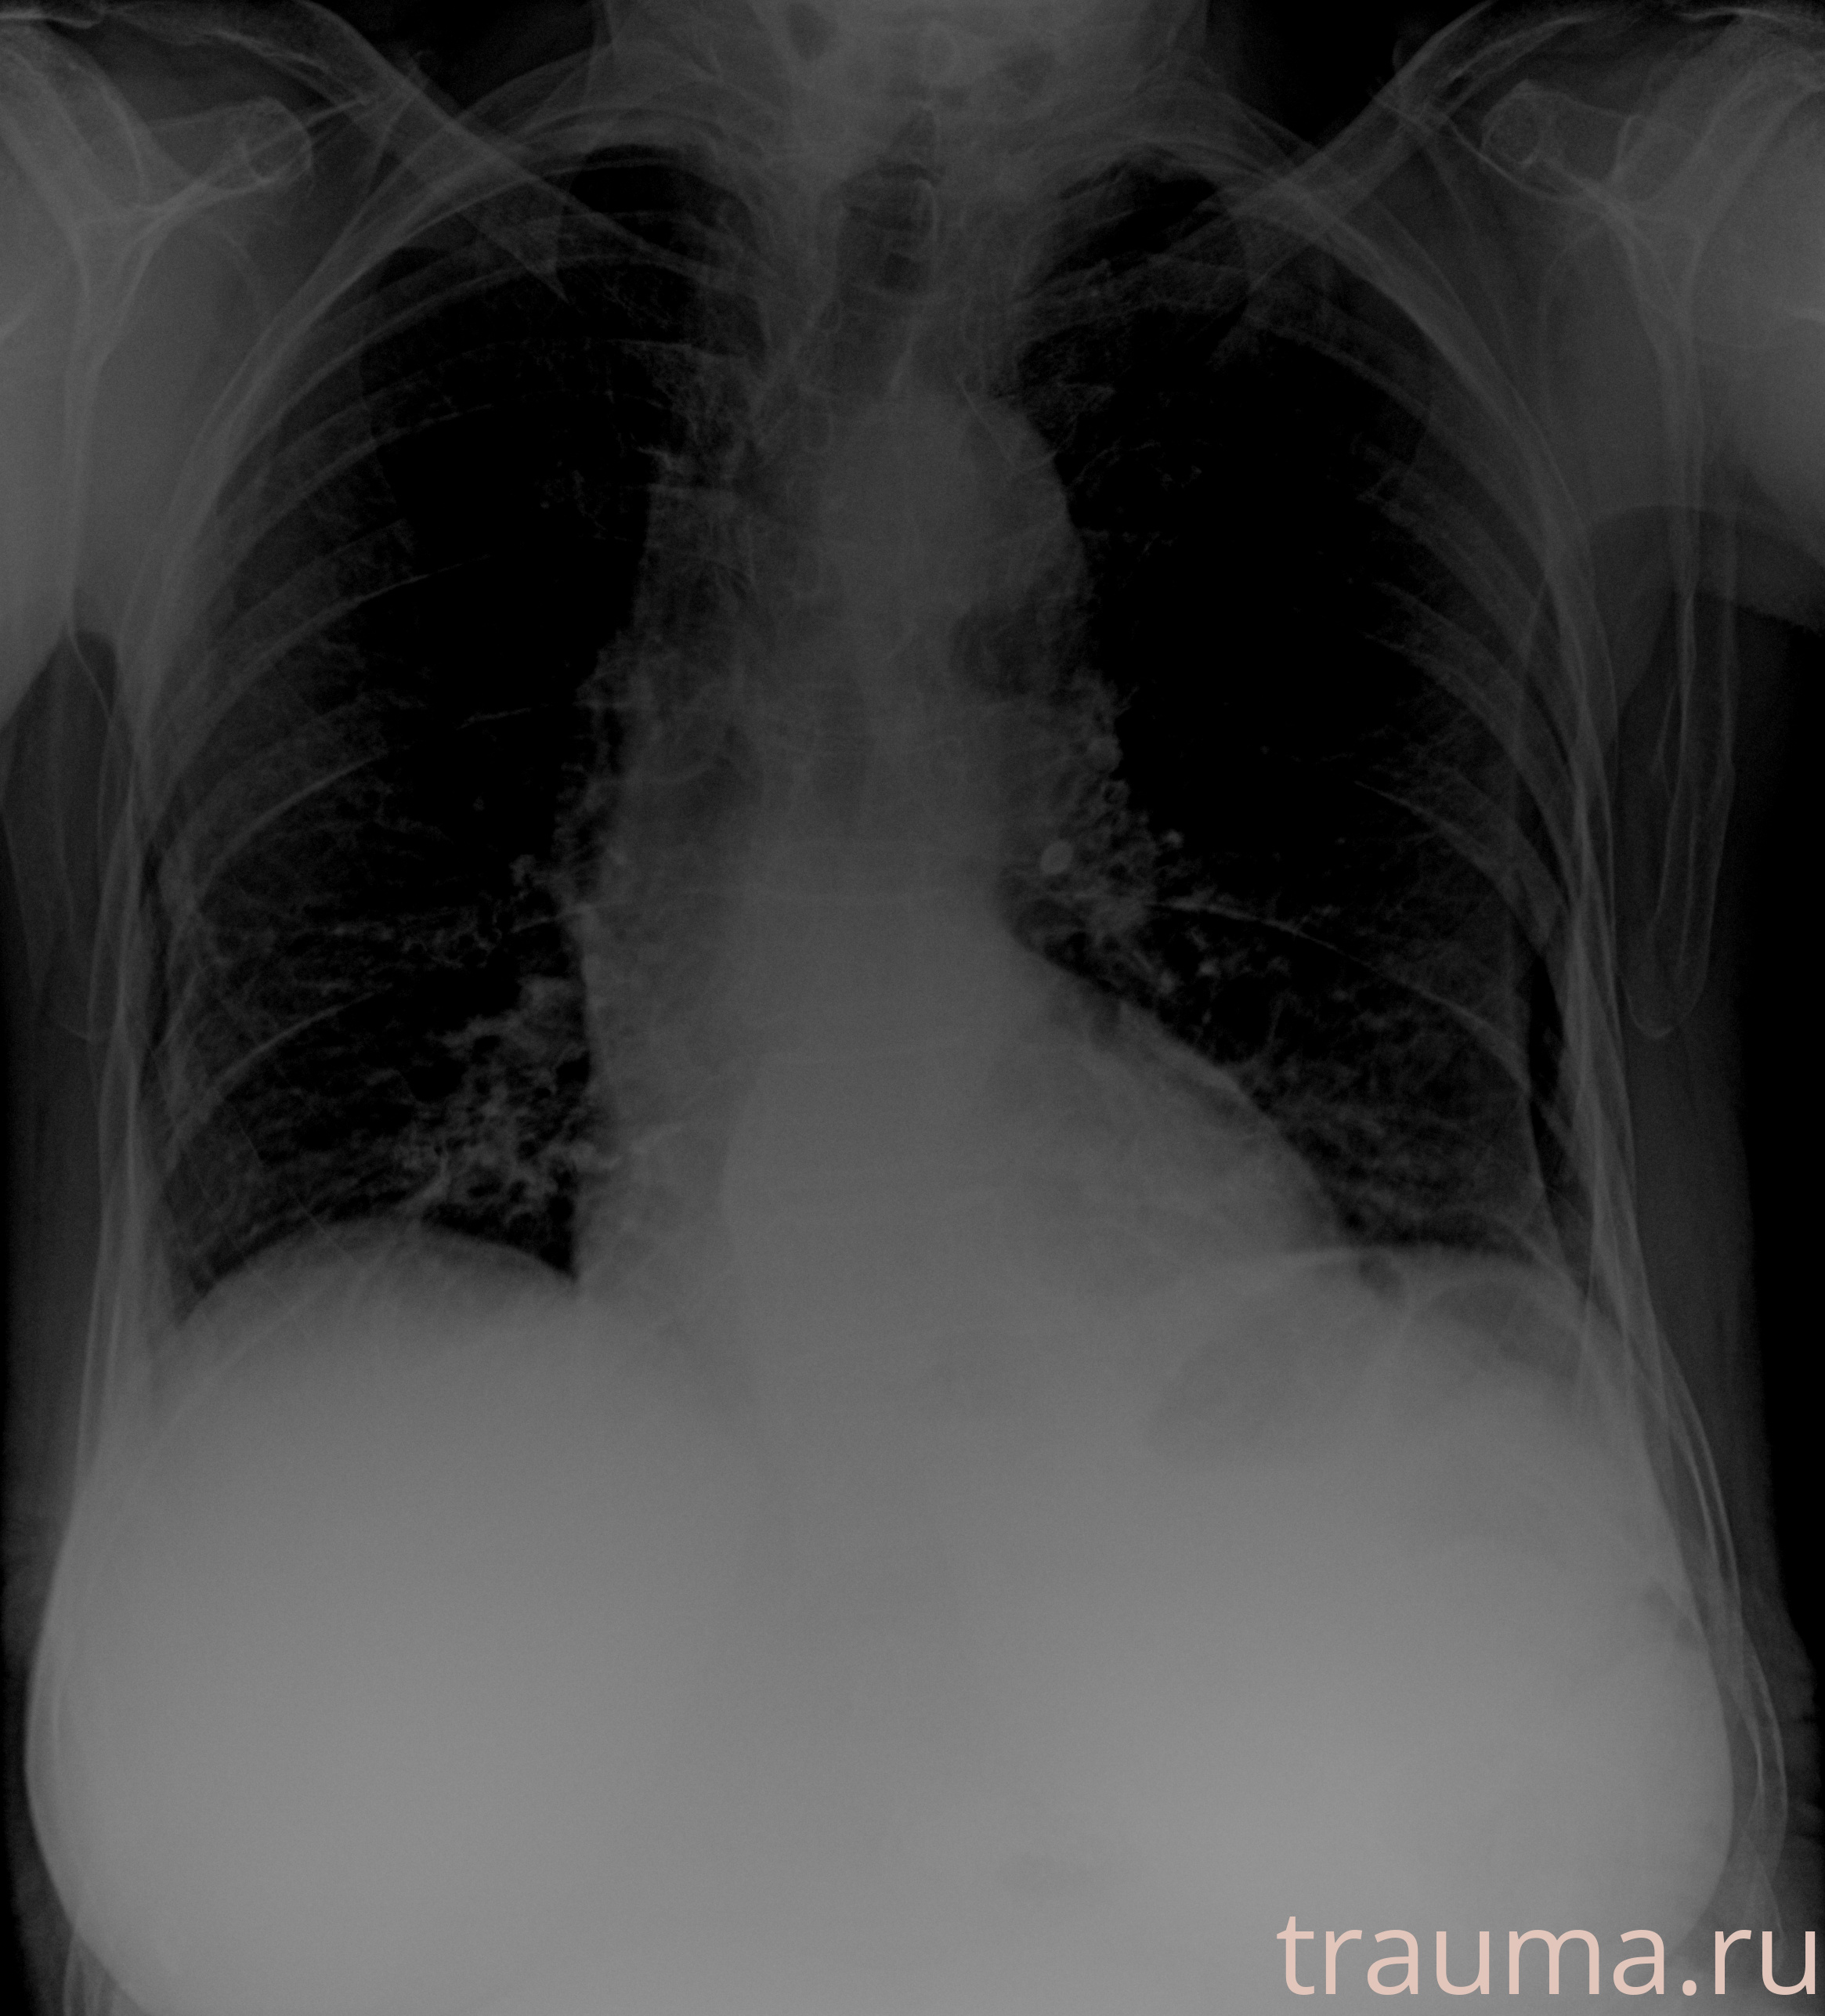

Рентгенограммы

Рентген на дому: по вашему адресу приезжает врач-рентгенолог, травматолог-ортопед с мобильным рентгеновским аппаратом, проводит диагностику травмы или заболевания, делает необходимые рентгенограммы, дает рекомендации по дальнейшему лечению. Получить качественные снимки в домашних условиях возможно благодаря уникальной методике, разработанной МосРентген Центром для института  Склифосовского

при переломе шейки бедра и пневмонии от компании МосРентген Центр - партнера Института имени Склифосовского